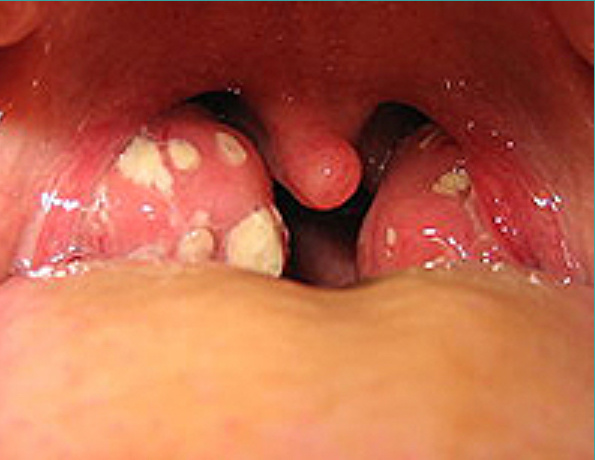

Ангина - инфекционно–аллергический процесс, локальные изменения при котором затрагивают глоточное лимфоидное кольцо, чаще всего небные миндалины. Течение ангины характеризуется повышением температуры тела, общеинтоксикационным синдромом, болью в горле при глотании, увеличением и болезненностью шейных лимфоузлов. При осмотре выявляется гиперемия и гипертрофия миндалин и небных дужек, иногда – гнойный налет. Ангина диагностируется отоларингологом на основании данных фарингоскопии и бактериологического посева из зева. При ангине показано местное лечение (полоскание горла, промывание лакун, обработка миндалин препаратами), антибиотикотерапия, физиотерапия.

Ангина – группа острых инфекционных заболеваний, которые сопровождаются воспалением одной или нескольких миндалин глоточного кольца. Как правило, поражаются нёбные миндалины. Реже воспаление развивается в носоглоточной, гортанной или язычной миндалинах. Возбудители болезни проникают в ткань миндалин извне (экзогенное инфицирование) или изнутри (эндогенное инфицирование). От человека человеку ангина передается воздушно-капельным или алиментарным (пищевым) путем. При эндогенном инфицировании микробы попадают в миндалины из кариозных зубов, придаточных пазух (при синуситах) или носовой полости. При ослаблении иммунитета ангина может вызываться бактериями и вирусами, которые постоянно присутствуют на слизистой рта и глотки.